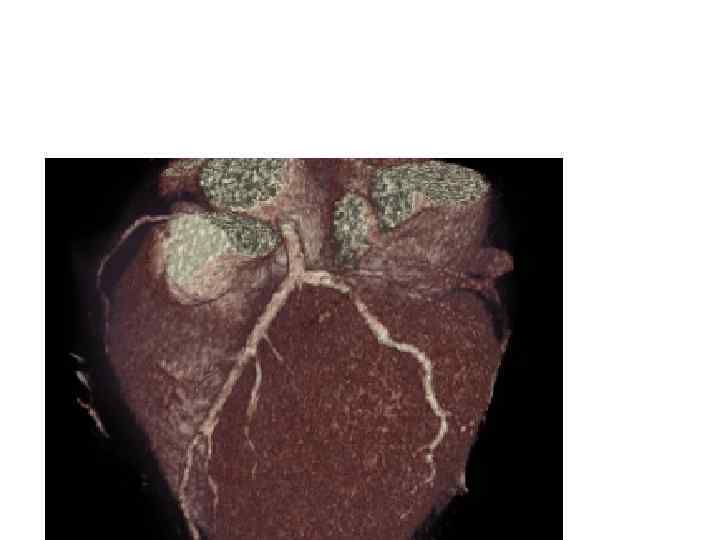

Жүректің компьютерлік томогаммасы

Жүректің компьютерлік томогамма 3 D өшемімен